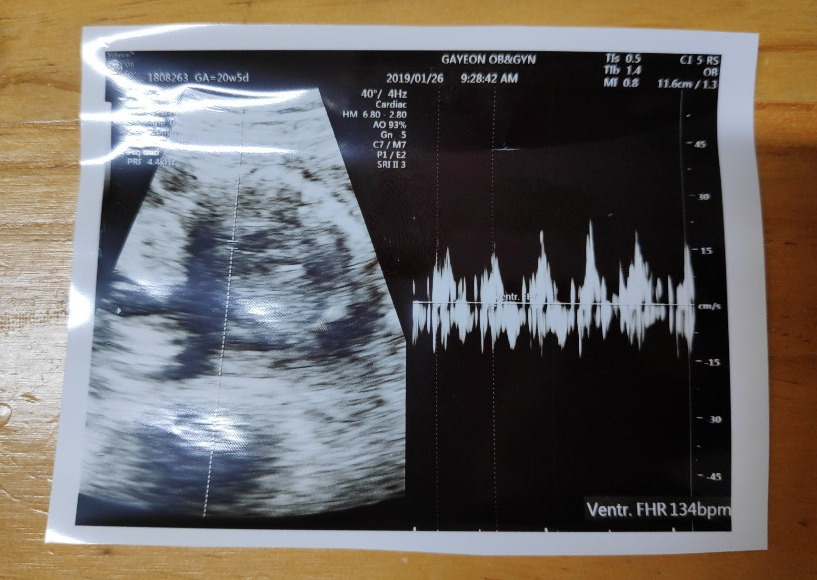

꼬톨이의 손과 발, 뇌, 장기 등이 정상적으로 자리 잡아가고 있는지를 보는 2차 정밀 초음파날!

초음파실에 들어가 하나하나 꼼꼼히 꼬톨이의 모습을 확인했다.

20분 정도 초음파를 본 것 같다. 손과 발 5개씩, 귀는 2개, 심장을 잘 뛰고 있는지.